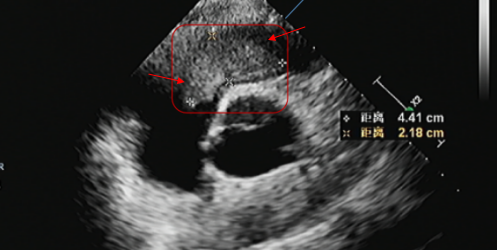

去年8月,李先生又感到胸闷及活动后气短,检查发现在右心室流出道又有新发粘液瘤,随后去外院就诊,进行了基因检测,提示为卡尼综合征(Carney 综合征)。近期自觉症状加重,超声检查显示肿瘤明显增大,堵塞右心室流出道血流,还有明显的三尖瓣关闭不全。为寻求进一步治疗,李先生来到西安高新医院心脏大血管外科。

术前影像显示,心腔内粘液瘤已明显增大